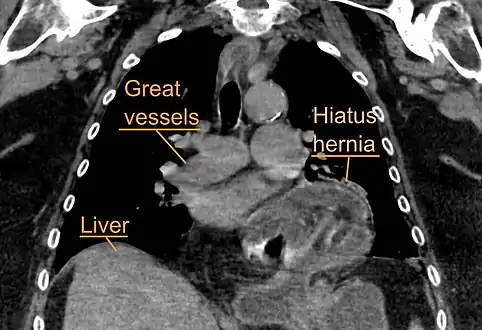

A hiatal hernia as seen on CT

A large hiatal hernia as seen on CT imaging